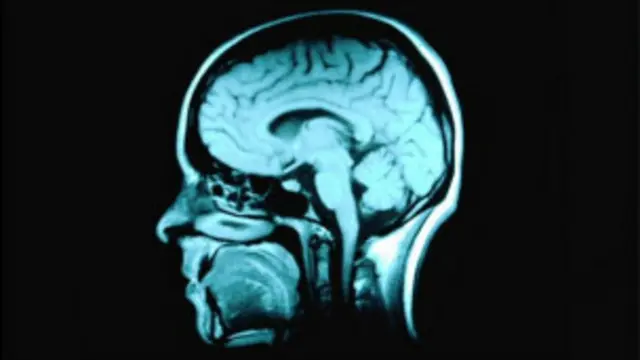

فمن خلال عمليات تصوير بالرنين المغناطيسي، توصل فريق من العلماء الكنديين إلى أن مركز المكافأة في المخ ينشط عندما يستمع الشخص إلى أغنية لولجديدة أول مرة.

وكل ذلك يحدث أثناء استلقاء المشاركين في هذه الدراسة داخل جهاز أشعة التصوير بالرنين المغناطيسي.

وبتحليل صور الأشعة، توصل العلماء إلى أن النواة المتكئة كانت "مبتهجة". وبناء على مستوى النشاط، كان بمقدور الباحثين التنبؤ بما إذا كان من المرجح أن يشتري الشخص الأغنية.